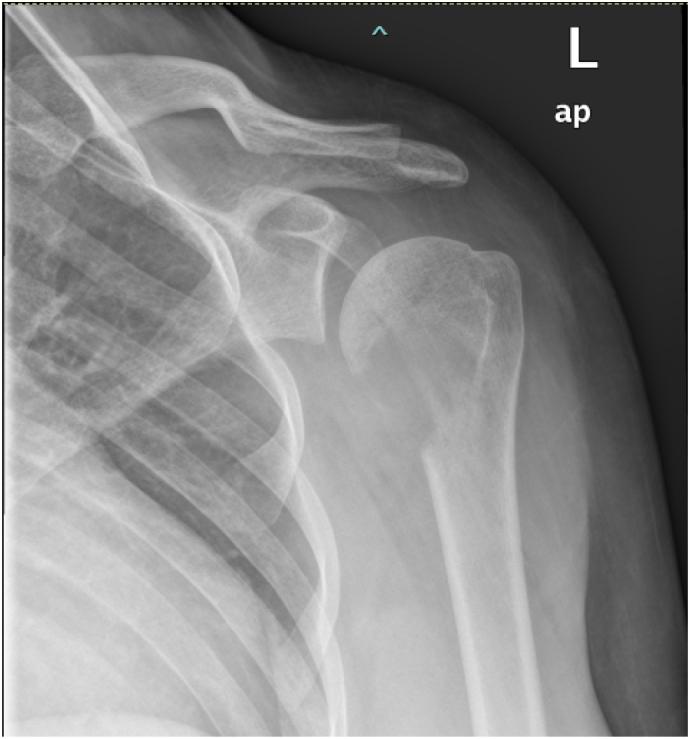

CASE PRESENTATION

We report a rare case of primary bony HS of the proximal humerus without bone marrow involvement in a healthy 33-year-old pregnant woman. She was successfully treated with surgical resection during pregnancy and radiotherapy post-delivery.

组织细胞肉瘤(HS)是一种罕见的、侵袭性的造血细胞源性恶性肿瘤。肱骨近端的原发性HS,无淋巴结或骨髓受累,亦无全身症状,极为罕见。

我们报告一例罕见的肱骨近端原发性骨HS病例,患者为一名33岁的健康孕妇,无骨髓受累。她在孕期接受了手术切除,并在产后接受了放疗,治疗成功。